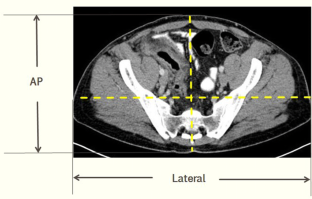

Fig. 4